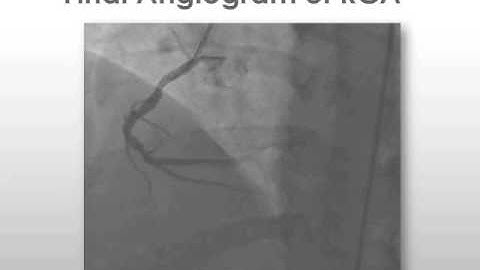

Using FFR to Identify the Culprit Lesion in Multivessel CAD